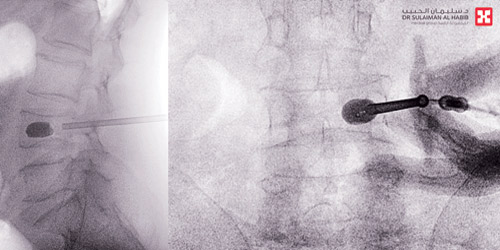

وأضاف د. محسن أن الفريق الطبي المعالج درس كافة النتائج ووضع خطة علاجية للمريض تتضمن التدخل الجراحي العاجل لإصلاح ورأب الكسر وتثبيته باستخدام تقنية «Kyphoplasty»، وهي من أحدث التقنيات وتختص بمعالجة مثل هذا النوع من الكسور بالعمود الفقري والأورام الكبيرة. وأشار إلى أن العملية استغرقت 45 دقيقة فقط، وتم فيها عمل فتحة صغيرة جداً في العمود الفقري بطول نصف سم، وإدخال بالون ونفخه بالفقرة المكسورة لتوفير مساحة لوضع مادة «أسمنتية» خاصة بالعظام، ومن ثم تثبيت الكسر وإعادة العمود الفقري لوضعه الطبيعي، مؤكداً على أن هذه التقنية تساعد بشكل كبير في تخفيف الألم وتحسين الحركة للمرضى بعد العملية، وبخاصة المصابون منهم بهشاشة العظام. وقال إن جهود الفريق الطبي تكلَّلت بالنجاح ولله الحمد، حيث أظهرت المؤشرات الحيوية تحسن حالة المريض منذ الساعات الأولى التي تلت الجراحة، واستطاع الحركة والمشي منذ اليوم الأول للعملية، وانتهت لديه كافة الأعراض السابق ذكرها، وقد غادر المريض المستشفى إلى منزله خلال 24 ساعة من دخوله المستشفى.